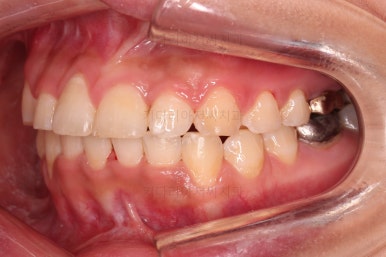

초진 시, 입 안의 모습이에요.

위아랫니가 삐뚤고 교합이 약간 맞지 않네요.

입 안만 보면 심플하게 교정하면 되겠다 싶지만, 문제는 다른 곳에 있었어요.